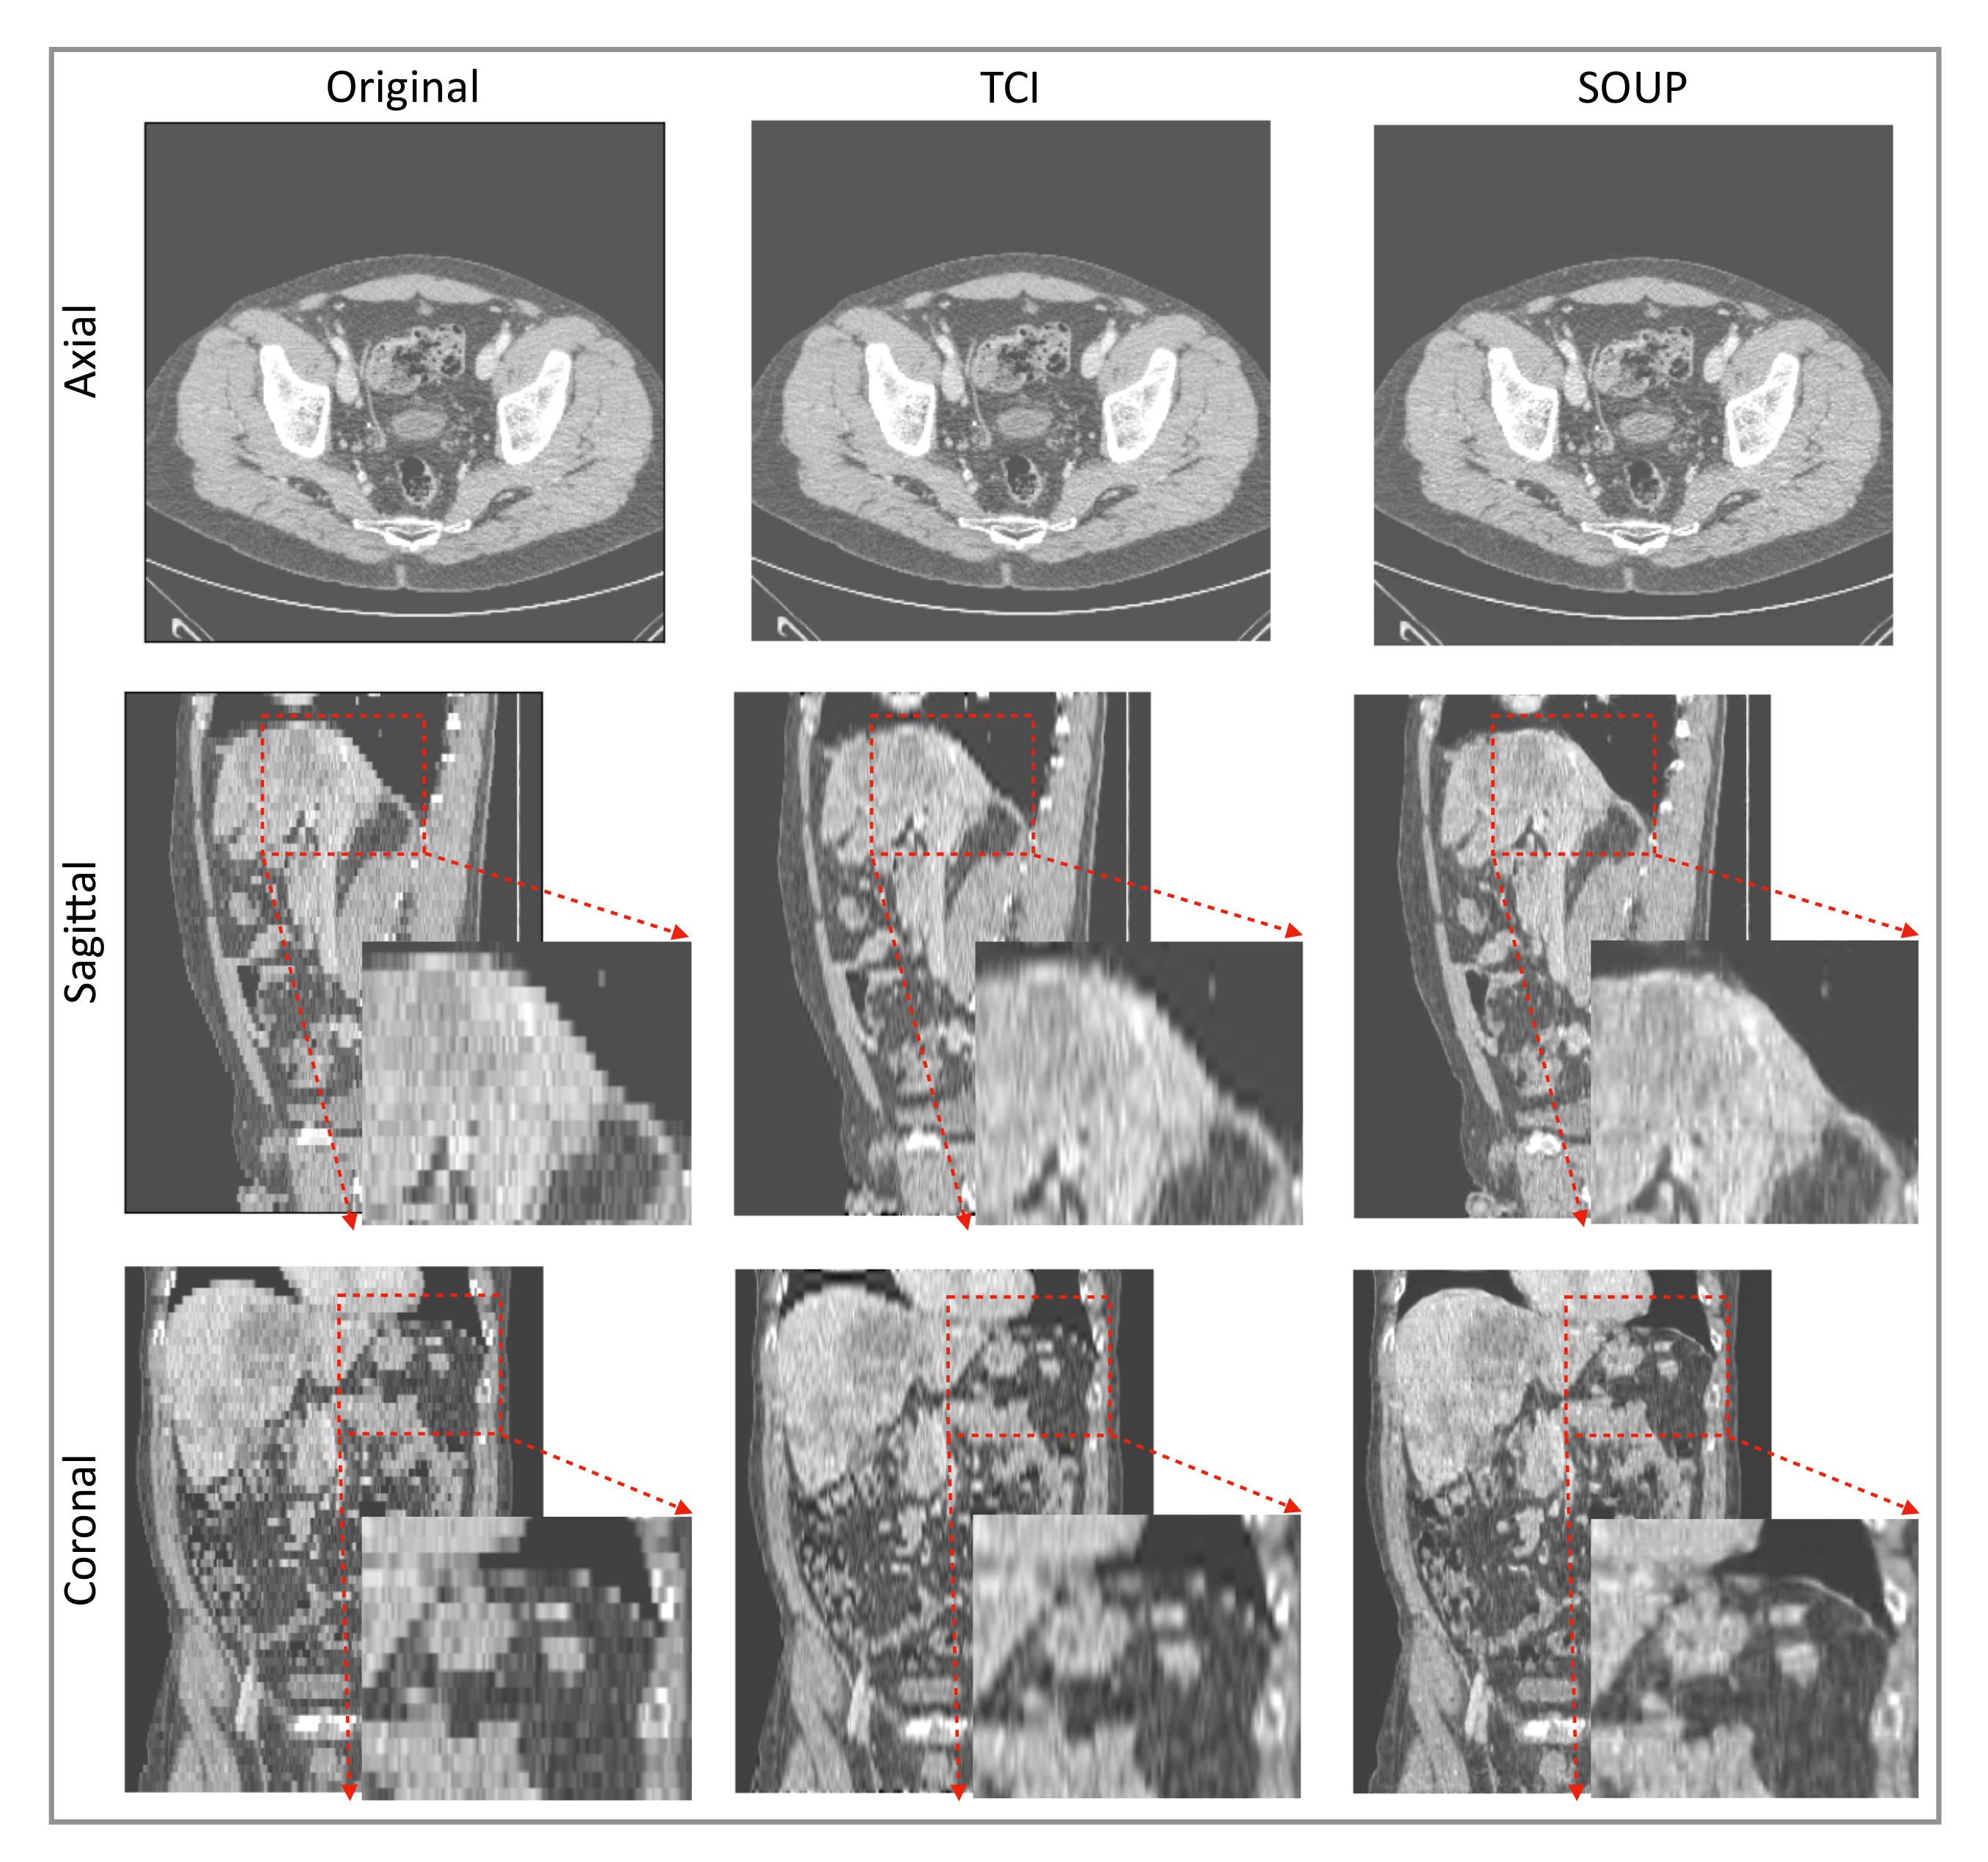

3.4. Generalization to Other Medical Imaging Modalities, e.g., CT

We also apply our scale-attention SR model to CT data. Figure 6 and Figure 7 show the SR-interpolated (SOUP) and conventionally interpolated images on abdominal and pelvic CTs. It is clear from both examples that the SR-interpolated results achieve significantly higher quality than the conventionally interpolated ones in regard to the edges, textual details, and blurring. Those comparisons demonstrate that our scale-attention SR model (SOUP) is a widely generalizable tool for different sampling factors and various applied imaging modalities, which paves the way for more advanced medical image interpolation through deep-learning SR.

Figure 7.

Another example of SR interpolation on CT data with a sampling factor equal to 5.72. TCI: tricubic interpolation.